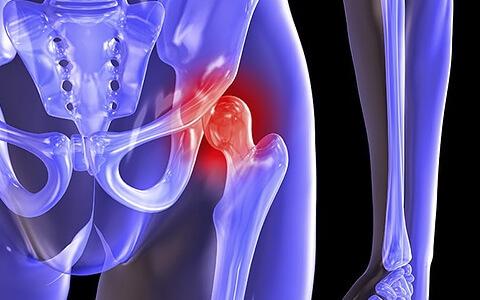

- В суставе пропадает активность и подвижность. Скованность наступает из-за сильного истощения сустава и хряща. Вначале у пациента происходит нарушение во вращательных движениях. После этого начинаются проблемы со сгибанием сустава, и подвижность теряется полностью;

- Часто слышится хруст кости при движении. Звук появляется из-за постоянного трения суставов друг об друга. Если заболевание усугубляется, тогда хруст усиливается;

- Сильные боли и прострелы в суставе. Приступ похож на ощущение прокалывания иголкой. Боль возникает из-за любого движения и активности. Если коксартроз на ранней стадии, тогда приступы проходят при расслаблении и отдыхе;

- Зажатость мышц в тазобедренной зоне. Боли и воспаления постепенно приводят к скованности в мышцах. Спазмы ощущаются в зоне бедра, ягодицы и поясницы;

- Одна нога становится на несколько сантиметров короче другой. Это происходит на запущенной стадии коксартроза. На глаз такое изменение не видно, только при измерениях врач может определить укорачивание ноги. Обычно изменение происходит на 1,5-2 см;

- У пациента начинается хромота. Проявляется на запущенной стадии заболевания и может вызвать осложнения. В этот момент пациент ощущает сильные боли, в суставе начинают разрастаться остеофиты. Если хромота не проходит, суставная капсула может полностью повредиться. Это приводит к переломам и частым вывихам.